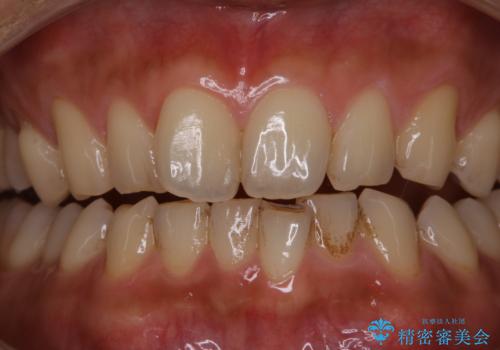

表のワイヤー装置で矯正中にPMTCで綺麗にお掃除

担当医 歯科衛生士